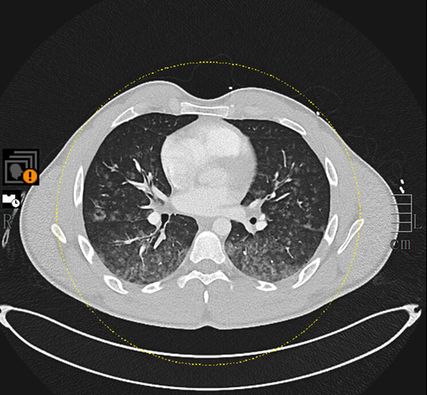

Dass Hämoptysen auch durch ungewöhnliche Aktivitäten verursacht werden können, zeigt der folgende Fallbericht. Ein junger Patient wurde bewusstlos und mit Blutspuren vorgefunden und in die Notfallambulanz gebracht. Nachdem unterschiedliche Differenzialdiagnosen ausgeschlossen werden konnten, ergab sich eine unvermutete Genese seiner Symptomatik.

Aktive Hämoptysen stellen einen häufigen pneumologischen Notfall dar und bedürfen im Verlauf oft einer Bronchoskopie zur Blutstillung und Diagnostik. Es gibt eine Vielzahl an möglichen Genesen, wobei im klinischen Alltag vor allem Tumorerkrankungen, entzündliche Prozesse, Lungenembolien und Gefässmalformationen häufige Ursachen darstellen. Eine äusserst seltene Ursache von Hämoptysen ist das Zerreissen von Kapillaren durch hohe transpulmonale Drücke bei extremen sportlichen Belastungen («exercise-induced pulmonary hemorrhage»).